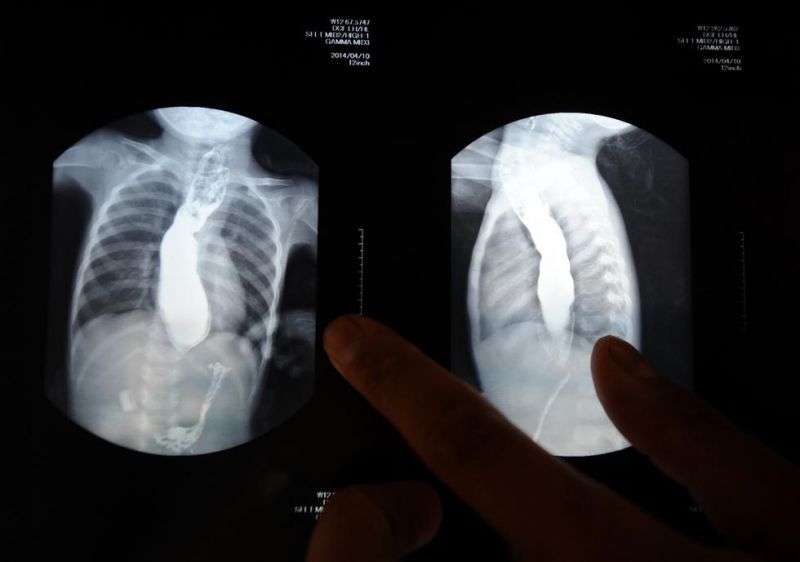

5月22日,王志華在展示女兒壹個月前拍的胸片,上面能清晰看到孩子的食管被撐得很大,食物卻無法進入胃部。由於王可然不停地嘔吐,這樣的喂食動作每天要重復無數次。500多天來,天天如此。王志華說,只要女兒能多吃壹口,他再苦再累也心甘。